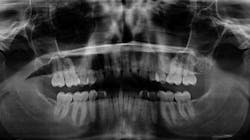

As it turned out, this young woman was at a very low risk for caries, and we agreed upon a two-year interval for her established care. The question that begs answering is this: what if she wasn’t a low caries risk?